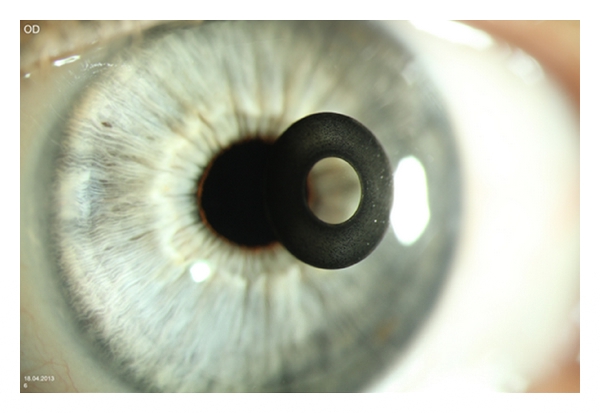

Кольцо вокруг глаз

Кольцо вокруг глаз 110 фотографий